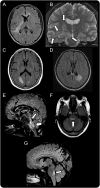

Figure 3. Brain MRI findings in patients with MOG-Ab

Extensive brain lesions with large diameter (A and B), posterior reversible encephalopathy–like lesions (C and D), and symmetric brainstem lesions involving pontine tegmentum (E–G) were found in the myelin oligodendrocyte glycoprotein antibody (MOG-Ab) group. A, C, D, F, and G = fluid-attenuated inversion recovery; B = T2-weighted image; E = double inversion recovery.